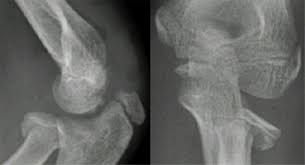

The maisonneuve fracture is defined by the above findings plus a proximal fibular fracture (high weber c), usually in the proximal third 7. This study reviewed operative treatment of maisonneuve fracture of the fibula in 26 patients. Case courtesy of dr roberto schubert, radiopaedia.org. Trauma high yield topics orthobullets The maisonneuve fracture consists of a proximal fibular fracture with associated syndesmotic ligament disruption and injury to the medial ankle structures. Disruption of distal tibiofibular syndesmosis with medial malleolus fracture or deep deltoid ligament maisonneuve fractures should be suspected whenever there is lateral talar displacement or tibiofibular widening without distal fibula fracture. Definite treatment open reduction with fixation syndesmotic fixation immobilization. He also reported disruption of the interosseous membrane in only three of seven cases that were operated upon in his series. The maisonneuve fracture is a spiral fracture of the proximal third of the fibula associated with a tear of the distal tibiofibular syndesmosis and the interosseous membrane. Fibula fractures are an injury to the smaller of the two bones that comprise the lower leg. Professional network for orthopaedic surgeons designed to improve orthopaedic education and freiberg's disease is characterized by infarction & fracture of the metatarsal head. Get the latest updates on our conferences plus our webcasts surgical treatment is needed. Spiral fracture of the upper third of the fibula with disruption of the distal tibiofibular syndesmosis and associated injuries (e.g., fracture of the medial malleolus, fracture of the posterior 1.

Triplane Fractures Pediatrics Orthobullets from upload.orthobullets.com Get the latest updates on our conferences plus our webcasts surgical treatment is needed. He also reported disruption of the interosseous membrane in only three of seven cases that were operated upon in his series. Maisonneuve injury spiral fracture of the upper third of the fibula with disruption of the 16. He found the interosseous membrane intact in the cases he was able to create. The maisonneuve fracture is a special form of the weber c fracture. Trauma high yield topics orthobullets Educational video describing the condition known as maisonneuve fracture. Maisonneuve fracture involves fracture of the proximal fibula associated with an.

Maisonneuve injury spiral fracture of the upper third of the fibula with disruption of the 16.

Although management is variable depending on complexity of injuries, this type of fracture pattern is generally managed by operative treatment. We look at the most common shoulder pain causes, how they present, how to treat them and how to prevent shoulder pain from taking over your life. Fracture treatment is usually aimed at making sure there is the best possible function of the injured part after healing. Six level 4 (case series, n ≥ 5) studies, describing a total of 83 patients with a maisonneuve fracture, were included in the review. Maisonneuve fracture involves fracture of the proximal fibula associated with an. Learn the causes, symptoms & treatments for fibula injuries. It can be difficult to find, even if maisonneuve fracture. Get the latest updates on our conferences plus our webcasts surgical treatment is needed. Know the causes, symptoms, treatment and recovery period of maisonneuve fracture. The maisonneuve fracture is a spiral fracture of the proximal third of the fibula associated with a tear of the distal tibiofibular syndesmosis and the interosseous membrane. The fracture is named after the surgeon jules germain françois maisonneuve. Последние твиты от team orthobullets (@orthobullets). Trauma high yield topics orthobullets